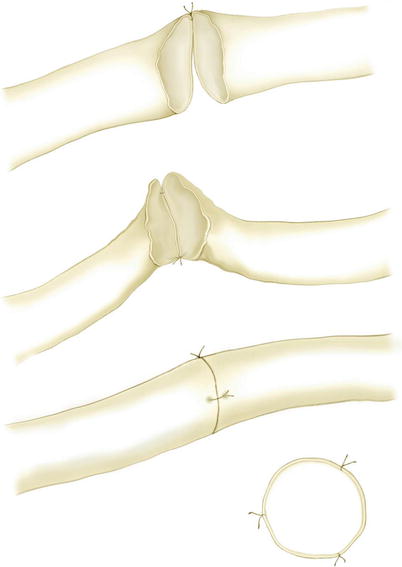

3.3.2 End-to-End Anastomosis

The two lymphatic vessels should be situated next to each other.

The first stitch is the most difficult one since the wall is collapsed. It might be helpful to add a small amount of Ringer’s solution mixed with heparin helping to lift the wall (Fig. 3.3). In very small lymphatic vessels with fibrosis around the lumen, it might be advisable to only fix the outer layer with the stitches. The content of the lumen of the vessel can then drain into the graft.

The back wall is just lifted when starting to anastomose. The first stitch is placed at the far end of the vessels.

The sutures are directed from outside to inside and back on the opposite wall.

The second corner stitch is placed in front of the surgeon.

The suture is finished with the closure of the front wall.

Care should always be taken to avoid tension to the lymphatic vessel wall in oblique direction.

In middle-sized lymphatic vessels, three to four stitches are enough.

Leakage will not be a problem since the pressure is low (Fig. 3.4).

In big or enlarged lymphatic vessels, around 6 to 8 stitches can be applied.

The graft is filled with lymph at the end of the anastomosis also when the wall of the lymphatic vessel within the edematous tissue shows fibrosis (Fig. 3.5).

End-to-end anastomosis with three stitches (© Baumeister)